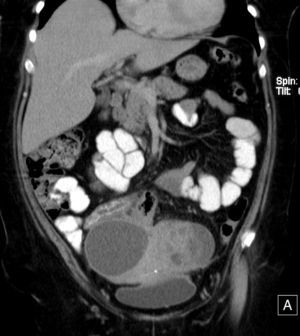

TC de abdomen y pelvis con contraste endovenoso en fase portal, y contraste oral positivo. Reconstrucción coronal. Lesiones sobre el útero, con relación al asa de íleon distal, con engrosamiento parietal concéntrico e hiperemia de la mucosa. Engrosamiento parietal del asa de colon sigmoides. DIU en cavidad endometrial.

Adyacente a las lesiones, se identifica un asa de íleon distal y una de colon sigmoides, engrosadas de forma concéntrica (fig. 2). Existe hidroureteronefrosis derecha asociada, con cambio de calibre y engrosamiento del urotelio con relación al cruce entre la lesión y los vasos ilíacos ipsilaterales (fig. 3).